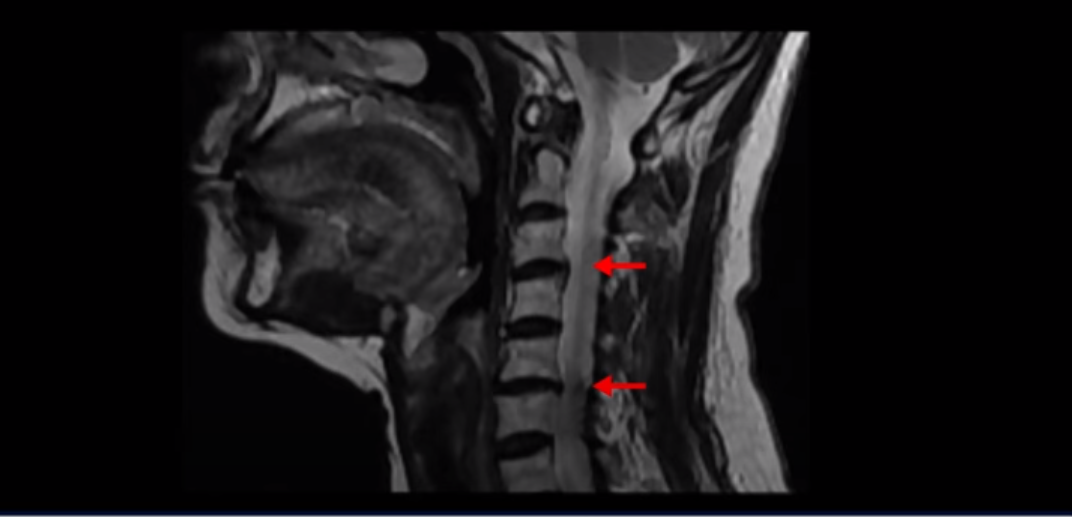

일반적으로 환자분들이 어지럽고 두통도 있고 하면 보통 이비인후과나 신경과에 많이들 가시는데, 목 문제 때문에 아픈 사람들은 당연히 이비인후과에서는 이상이 없다는 얘기를 듣고 또 신경과에서도 아무 이상이 없다고 듣거나 혹은 후두신경통을 진단받는 경우가 많습니다. 또 만성적으로 목과 어깨 근육이 뭉치면서 목 통증, 어깨통증이 있기 때문에 정형외과나 통증의학과, 한의원 등에 가면 근막통증증후군 같은 진단을 받는 경우도 많습니다. 게다가 이렇게 목이 아픈 환자분들은 척추병원에 가서 MRI를 찍어보면 이 환자분처럼 40세가 넘은 분들은 퇴행성 목디스크가 보이는 경우가 매우 많습니다.

이 환자분도 역시 이렇게 목디스크가 보이기 때문에 척추병원에서 목디스크 때문이라는 얘기를 듣고 신경 주사를 여러 번 맞게 되지만 목디스크 때문에 아픈 게 아니기 때문에 목디스크를 계속 치료해봐야 좋아지지 않는 겁니다.